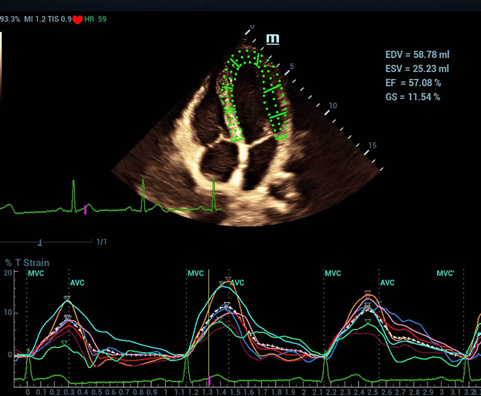

Desde su creaciÃģn, Mindray no ha dejado de explorar nuevas maneras de mejorar la fiabilidad del diagnÃģstico. Gracias a ZONE Sonography?, la tecnologÃa mÃĄs revolucionaria, la nueva plataforma ZST+ del Resona 7 eleva la calidad de imagen de ultrasonido mediante la adquisiciÃģn de zonas y el procesamiento de datos de canal.

AdemÃĄs de una calidad superior de la imagen, el Resona 7 tambiÃĐn mejora las capacidades de investigaciÃģn clÃnica gracias al revolucionario V Flow para la evaluaciÃģn hemodinÃĄmica vascular y la adquisiciÃģn de planos mÃĄs inteligente a partir de un conjunto de datos 3D para el diagnÃģstico CNS fetal. Combinando el funcionamiento multitÃĄctil mÃĄs intuitivo basado en gestos y todas las funciones clÃnicas esenciales, el Resona 7 estÃĄ realmente encabezando nuevas ondas en la innovaciÃģn del campo del ultrasonido.